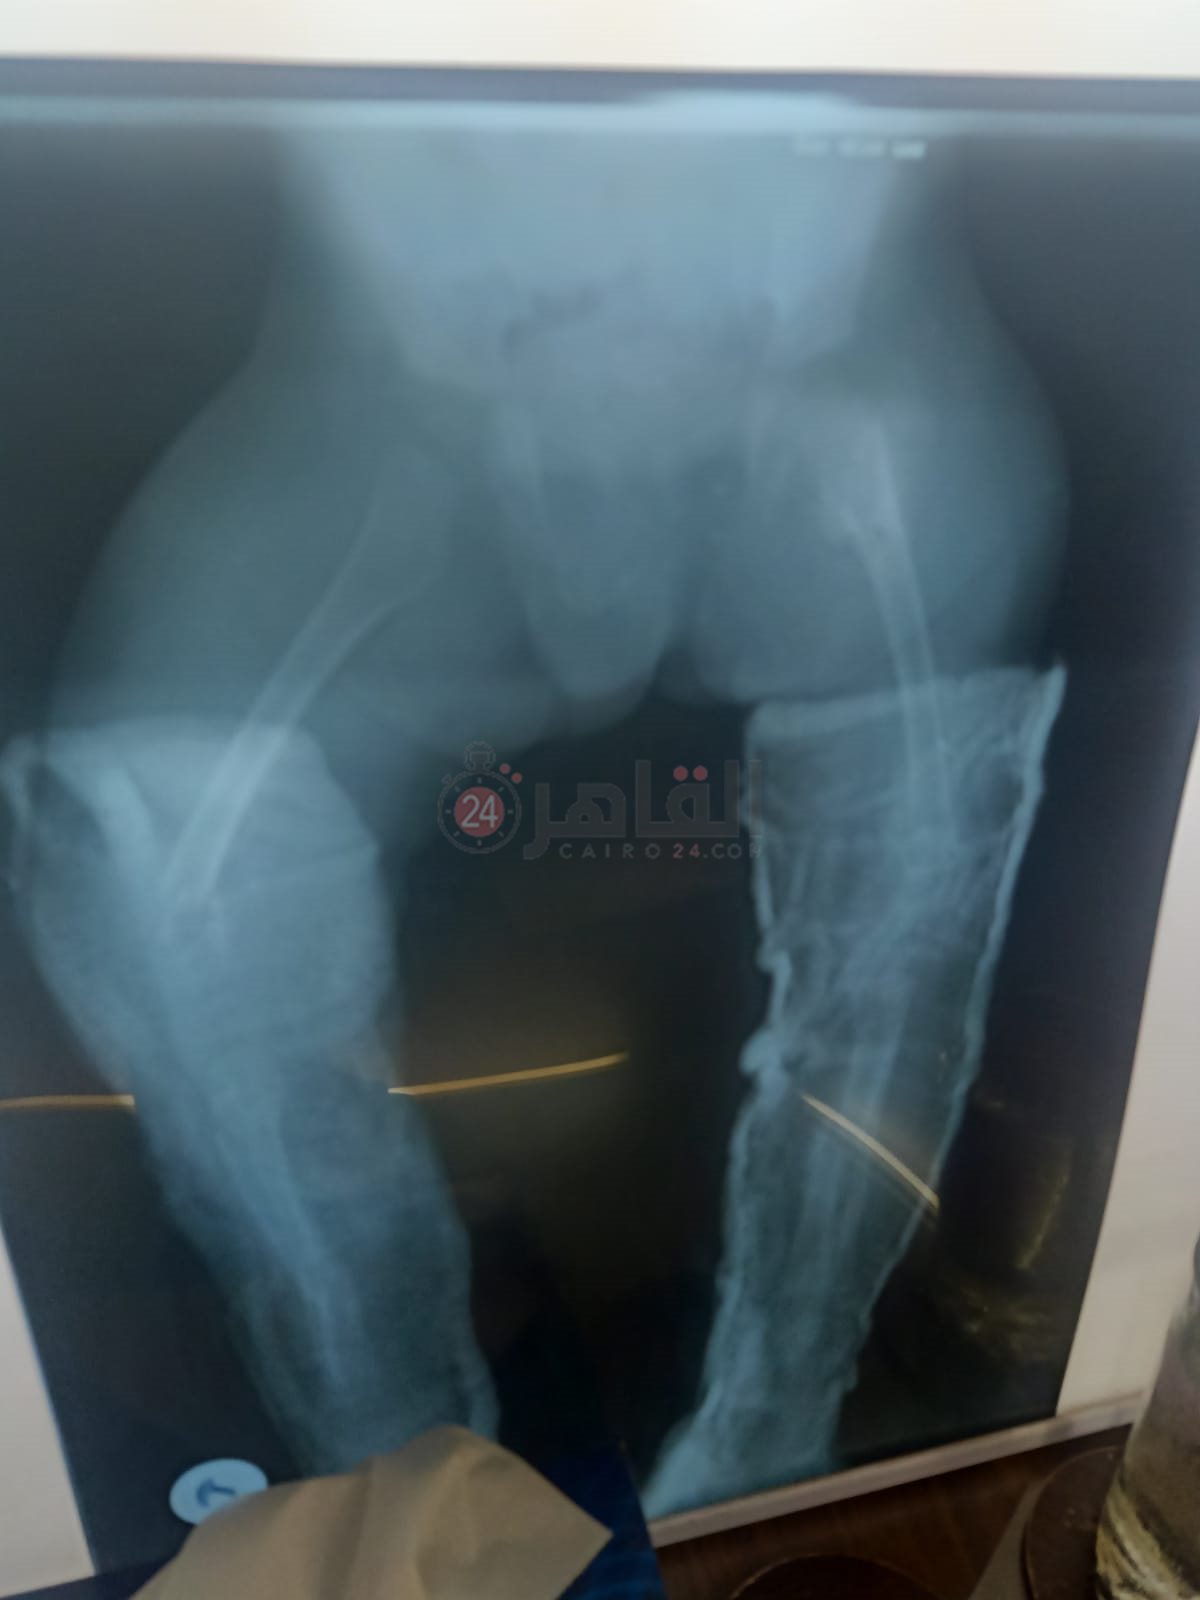

ريان طفل بالمنوفية يعاني من مرض العظم الزجاجي والذي يجعله عرضه لكسر العظام بشكل متكرر، صاحب الثلاث سنوات ونصف تعرض للكسر ما يزيد عن 51 مرة، في كل أطراف الجسم بالإضافة إلى خضوعه لعملية جراحية لتركيب مسمار مطاطي نخاعي في الذراع الأيمن ويحتاج لعملية جراحية أخرى لتركيب نفس المسمار في الذراع الأيسر خلال 15 يوما على الأكثر.

وتروي والدة ريان لـ القاهرة 24 مأساة ابنها صاحب الثلاث سنوات ونصف، والذي يتعرض للكسور بشكل متواصل، وتؤكد على حجم المعاناة التي تعرض لها الصغير حيث تعرض ذراعه الأيمن لـ 21 كسرا، والذراع الأيسر 18 كسرا وكل قدم من أقدامه 6 كسور بالإضافة إلى تجبيس كامل في القدمين بـ 5 بناطيل من الجبس.